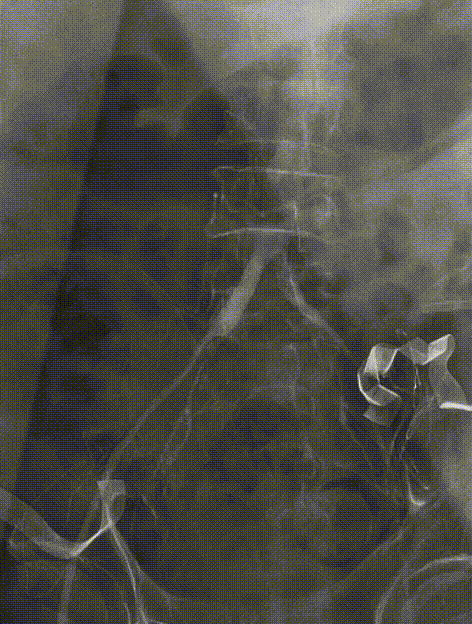

主动脉根部造影。

Numed18mm球囊扩张主动脉瓣。

VenusA-Plus®L23瓣膜置入及释放。

最后造影,瓣膜位置良好,未见反流。